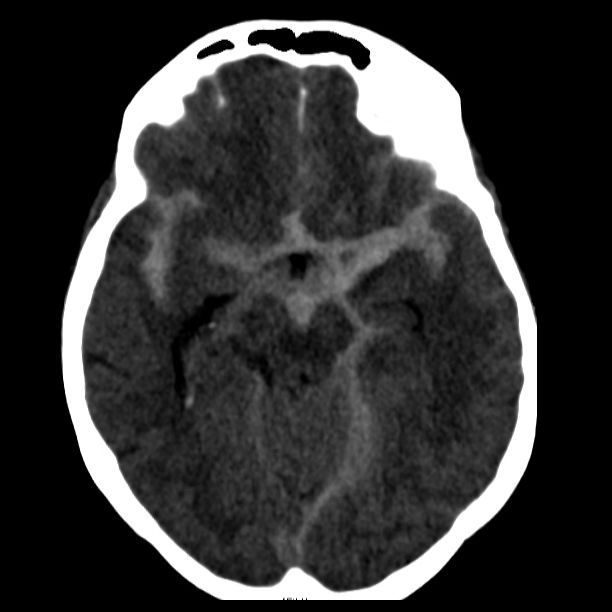

Als schnellste und sicherste Maßnahme gilt das craniale Computertomogramm (CCT). Hier lässt sich eine frische SAB meist zuverlässig darstellen, wobei auch bereits richtungsweisende Befunde, wie das Ausmaß der Blutung und eine eventuelle Lokalisation eines möglichen Aneurysmas bestimmt werden können. Darüber hinaus kann ein Angio-CCT, bei dem zusätzlich Kontrastmittel verabreicht wird und dann die intrazerebralen Blutgefäße gesondert rekonstruiert und dargestellt werden, weitere Informationen liefern. Der sogenannte “Goldstandard” zur Diagnose zerebraler Gefäßmissbildungen ist jedoch die zerebrale Angiographie. Dabei wird mit Hilfe eines speziellen Katheters über die Leisten- oder Armarterie Kontrastmittel gegeben und die zerebralen Blutgefäße hoch selektiv dargestellt. Sollten sich auf dem initialen CCT Zeichen des Hirnwasseraufstaus zeigen, der durch ein Verstopfen der Abflusskanäle durch das neu aufgetretene Blut bedingt ist, ist oft die Anlage einer Hirnwasserableitung nach außen notwendig (externe Ventrikeldrainage).

Als diagnostische Maßnahme wird in der Regel ein craniales Computertomogramm (CCT) durchgeführt. Intrazerebrale Blutungen lassen sich mit dieser Methode sicher diagnostizieren.

Je nach Lokalisation und Ausdehnung der Blutung und in Abhängigkeit vom klinischen Zustand des Patienten muss entschieden werden, ob eine chirurgische Intervention notwendig ist. In diesem Falle wird über eine Eröffnung der Schädeldecke die Blutung in mikrochirurgischer Technik entfernt.

Bild einer intracerebralen Blutung nach OP.

Bild einer intracerebralen Blutung vor OP.